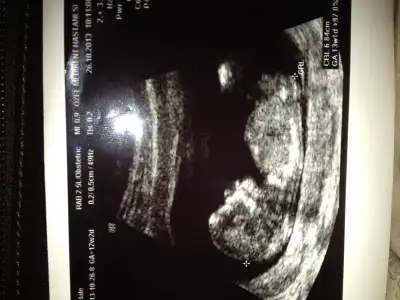

kızlar 12 haftalık bakın bakalım dr. Pipiye benzer bişey görüyrm dedi ama sizce nasıl????